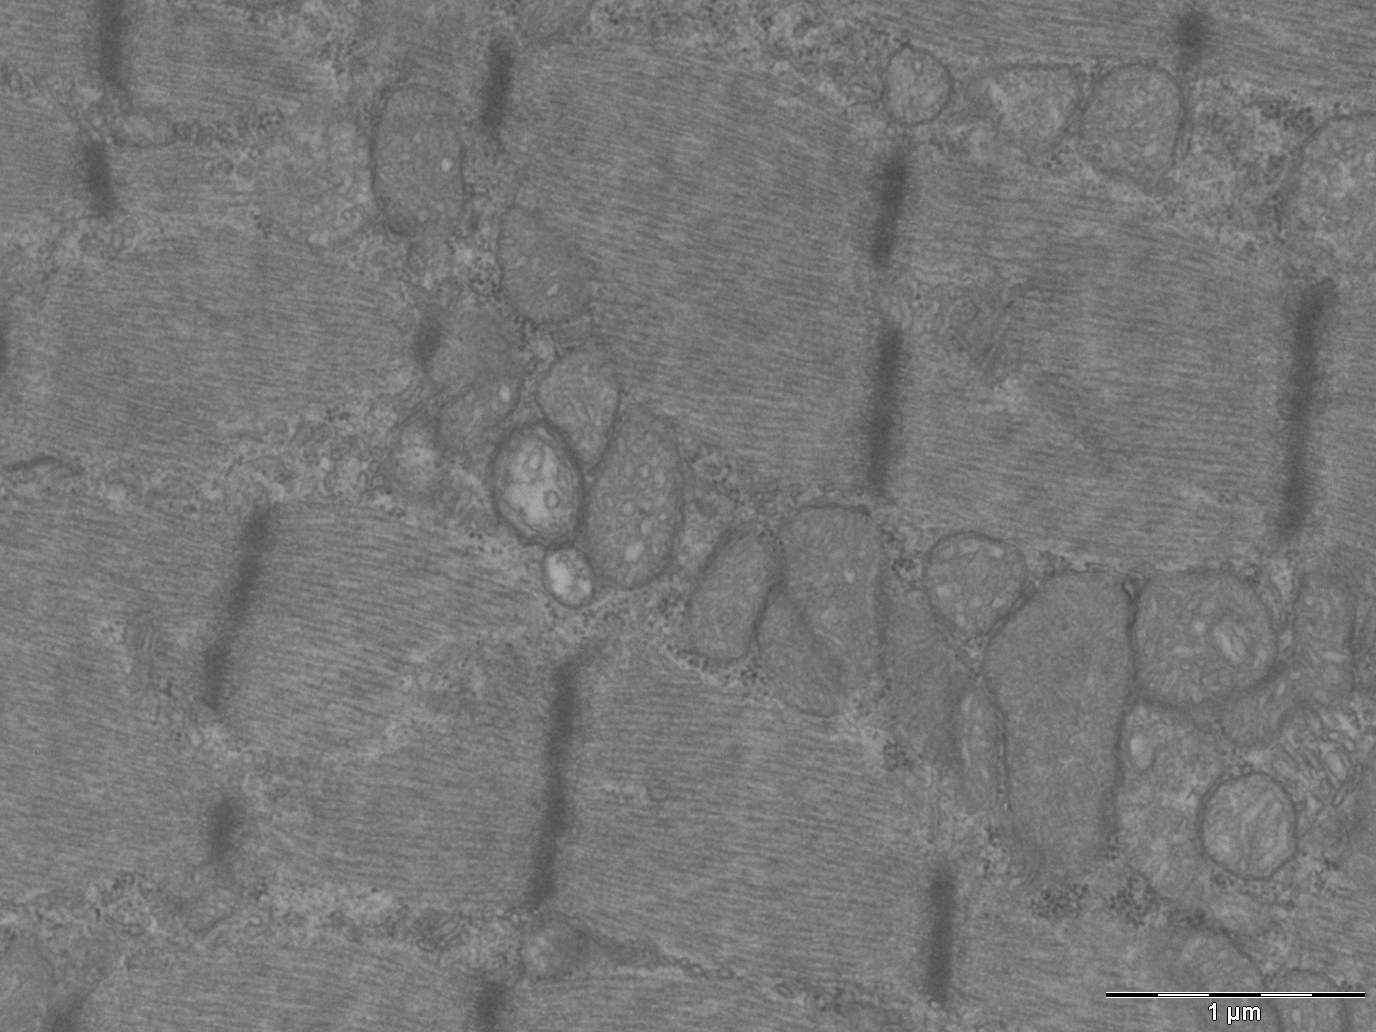

Opa1 is a mitochondrial fusion protein. It serves to fuse the internal membranes of mitochondria. Although present in all cells and tissues (except red blood cells), mitochondria are particularly abundant in muscle and liver, and their main function is to convert the energy in food into energy for cells. Mitochondria are highly dynamic; they join and separate, and grow and shrink constantly. These processes are known as mitochondrial dynamics.

The article describes the animal phenotype and explains that the removal of Opa1 exclusively from skeletal muscle fibre triggers a severe inflammatory process that spreads from the muscle fibre throughout the body. The inflammatory response halts growth and shortens the lifespan of the animal. The scientists also describe the main molecular components of the cell signalling pathway that activates the inflammatory response in muscle.

The head of the study explains that these results are of biomedical relevance. There is a set of diseases known as inflammatory myopathies, of unknown origin, in which patients show chronic muscle inflammation accompanied by muscle weakness. "The results of this study suggest that mitochondrial alterations may underlie inflammatory myopathies. More research is now needed to address this possible link," says the scientist.